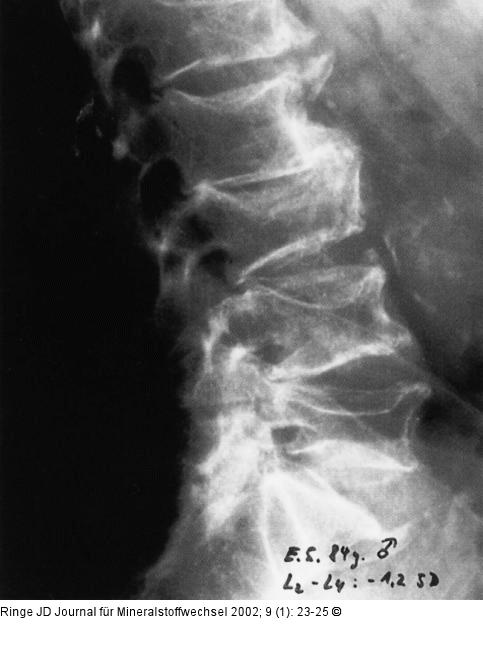

Abbildung 4: Osteoporose - Fraktur - Spondylose Seitliche LWS eines 84jährigen Mannes mit älteren osteoporotischen Frakturen und sek. Spondylosis deformans: ventrale Spondylophyten bei L1/2 und Spangenbildung bei L2/3. |

Seitliche LWS eines 84jährigen Mannes mit älteren osteoporotischen Frakturen und sek. Spondylosis deformans: ventrale Spondylophyten bei L1/2 und Spangenbildung bei L2/3. |